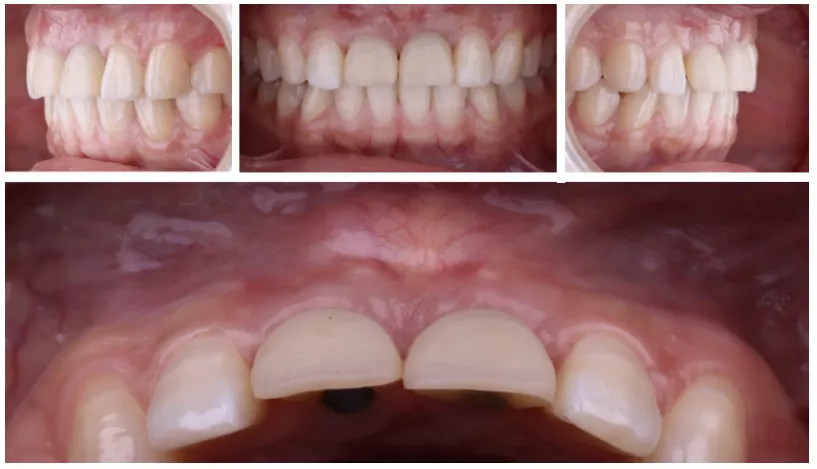

·      植体植入三个月后,制作临时修复体,穿龈塑形。

定期检查,评估植体及牙龈情况

·     佩戴两个月后复查。

·     检查唇齿关系。

·     DSD。

制取印模,制作最终修复体

·      个性化印模杆制取穿龈形态,制作最终修复体。

修复体试戴及粘接